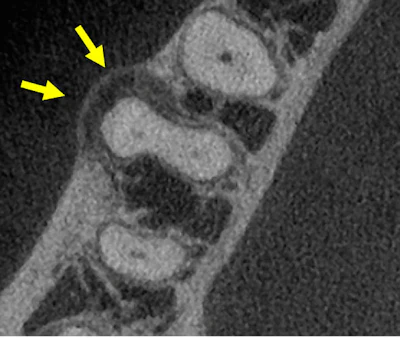

Figure 2: CBCT, axial view (tooth #30).

Small hypodense lesions (radiolucent) are observed at the mesial and distal apices of tooth #30. The lesions are well defined and well corticated. There is no evidence of expansion in the coronal and axial projections for the small lesion at the distal apex. However, there is evidence of expansion (buccal) of the hypodense lesion located at the apex of the mesial root. Hyperdense bone is present at the periphery of the lesion, indicating a chronic inflammatory process.